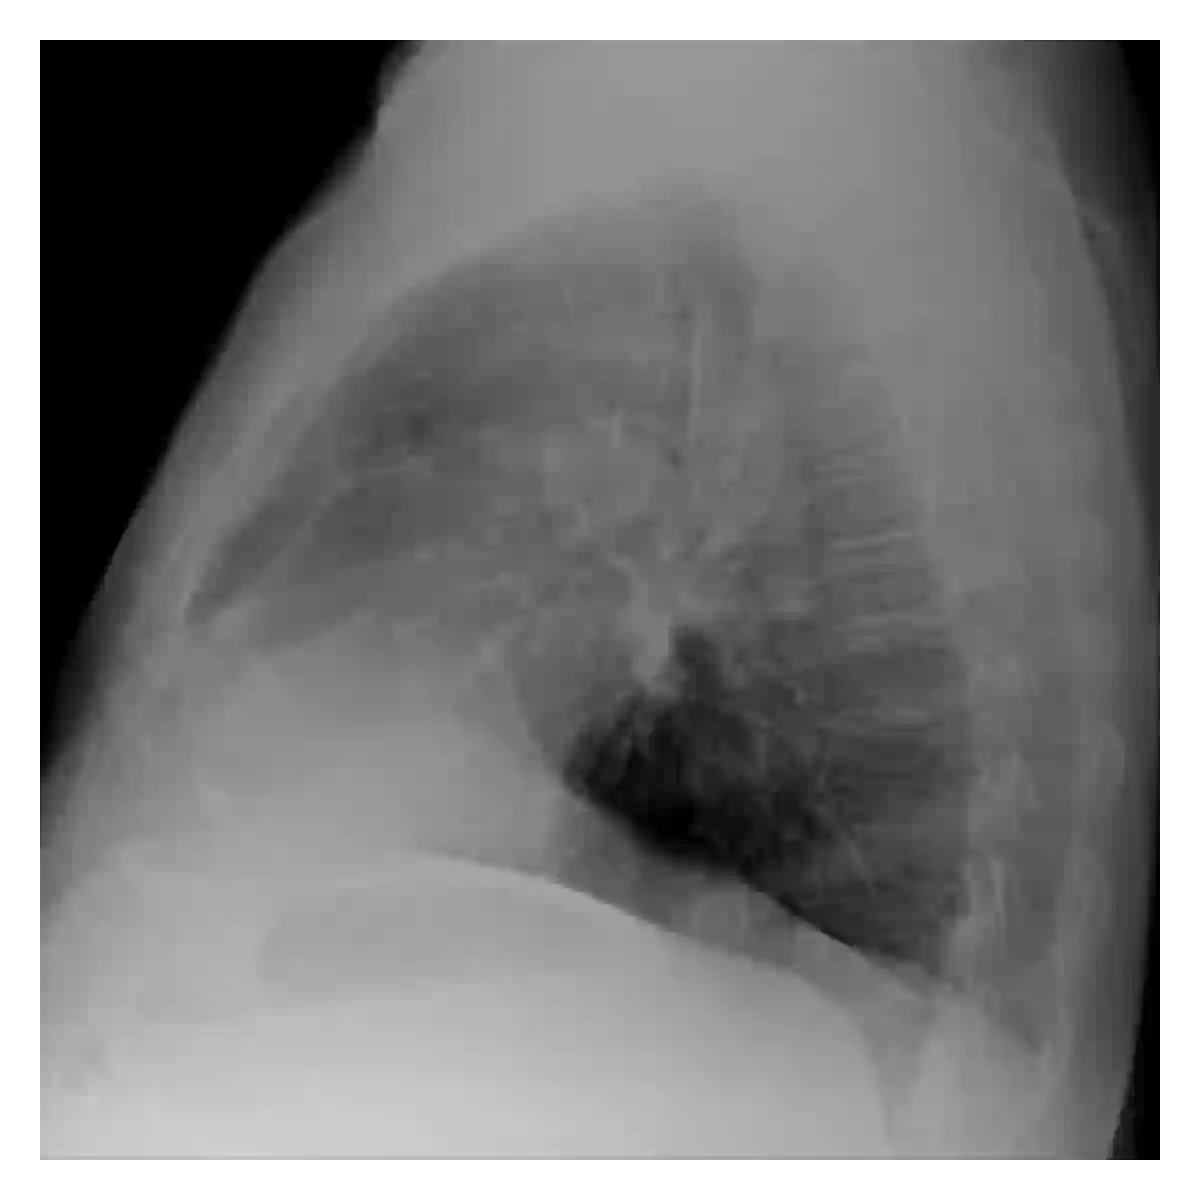

The evaluation of infectious disease processes on radiologic images is an important and challenging task in medical image analysis. Pulmonary infections can often be best imaged and evaluated through computed tomography (CT) scans, which are often not available in low-resource environments and difficult to obtain for critically ill patients. On the other hand, X-ray, a different type of imaging procedure, is inexpensive, often available at the bedside and more widely available, but offers a simpler, two dimensional image. We show that by relying on a model that learns to generate CT images from X-rays synthetically, we can improve the automatic disease classification accuracy and provide clinicians with a different look at the pulmonary disease process. Specifically, we investigate Tuberculosis (TB), a deadly bacterial infectious disease that predominantly affects the lungs, but also other organ systems. We show that relying on synthetically generated CT improves TB identification by 7.50% and distinguishes TB properties up to 12.16% better than the X-ray baseline.